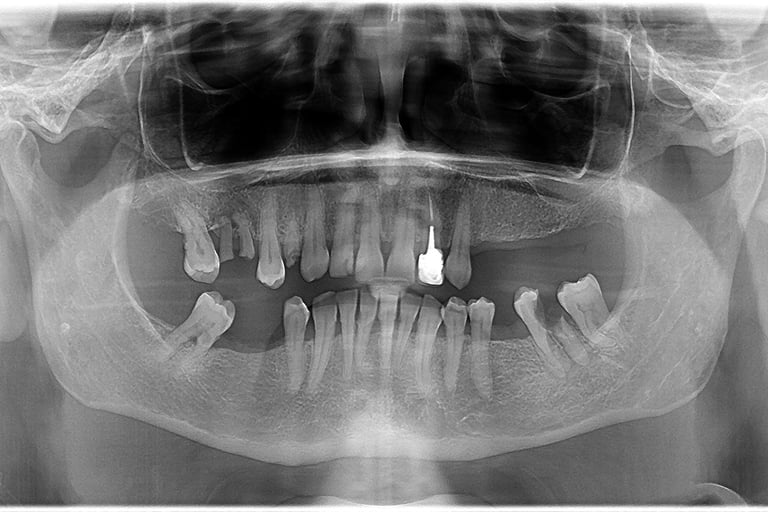

Se deceleaza imagistic o formatiune tumorala radiotransparenta, de mari dimensiuni, localizata la nivelul intregului grup frontal mandibular.

Dupa examenul clinic si imagistic se pune diagnosticul prezumtiv de formatiune tumorala chistica (chist radicular de mari dimensiuni). Se intervine chirurgical realizandu-se extractiile dintilor cauzali, irecuperabili, rezectii apicale a dintilor implicati chistic, care au fost tratati endodontic in prealabil. Piesa operatorie a fost trimisa catre examenul histopatologic, diagnosticul fiind chist radicular fara atipii.